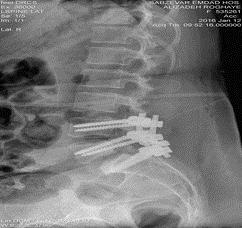

یک مورد از عمل موفقی که با تشخیص پارگی دیسک اسپوند یلولیستزیس گرید 3وتنگی کانال نخاع لومبار توسط اقای دکتر نوبری تحت عمل جراحی قرارگرفته اند و بعد از عمل جراحی تمام علائم بی حرکتی اندام تحتانی درد شدید وبی حسی اندام تحتانی وی برطرف شده به شرح ذیل می باشد.

بیمار مرضیه طزری61 ساله بابحسی شدید هردو اندام درد شدید وبی حرکتی هردو پا وبا تشخیص تنگی کانال نخاع توراسیک در بیمارستان بستری وبعداز انجام عمل جراحی لامینکتومی ، فاشکتومی مدیال دوطرف فورامینتومی دو طرفه با پیچ ومیله پدیکول دو طرفه توسط دکترنوبری بیمارفوق بعد از 4روز بستری در بخش جراحی اعصاب بیمارستان تمام علائم فوق برطرف شد وبیمار با پای خود مرخص شد و از عمل خود احساس رضایت داشت .

"قبل عمل"

"بعد از عمل"